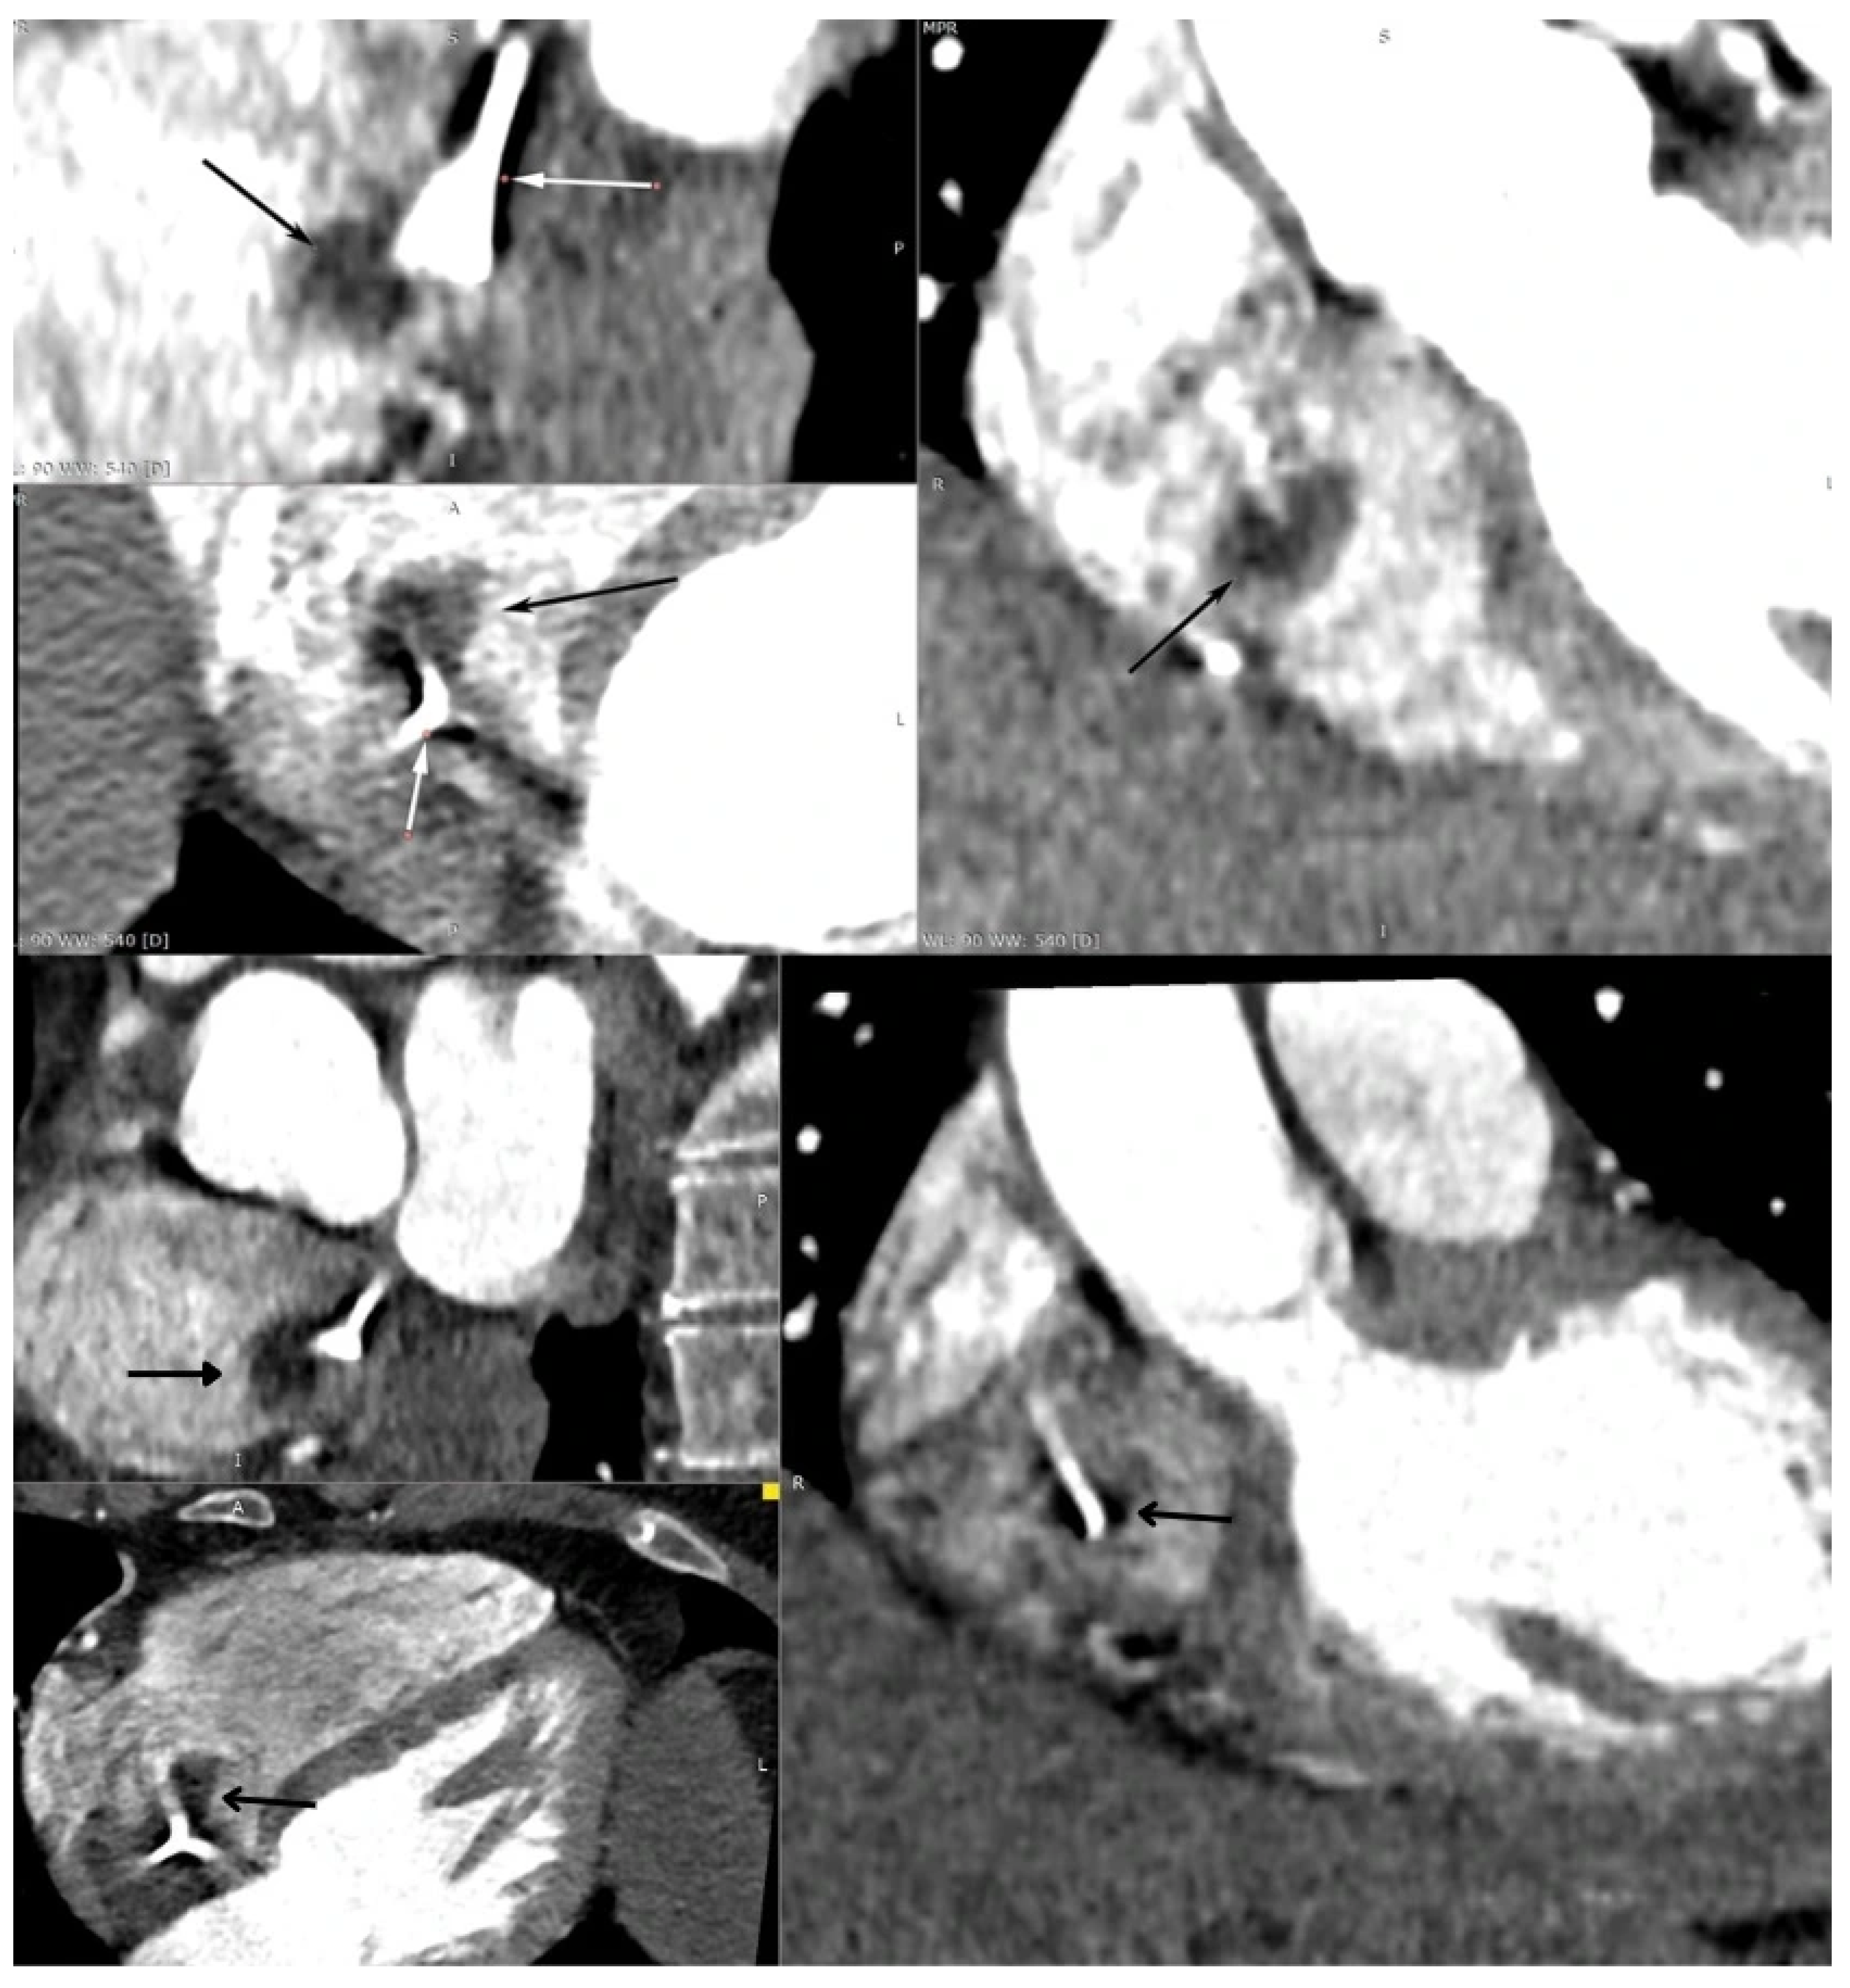

A Multi-Modality Approach to the Assessment of a Right Atrium Mass in a Female Patient with Breast Cancer Undergoing Neoadjuvant Chemotherapy

Chlabicz, M.; Muszyński, P.; Kruszyńska, J.; Kazberuk, P.; Róg-Makal, M.; Lipowicz, M.; Matys, U.; Tomaszuk-Kazberuk, A.; Kożuch, M.; Dobrzycki, S. A Multi-Modality Approach to the Assessment of a Right Atrium Mass in a Female Patient with Breast Cancer Undergoing Neoadjuvant Chemotherapy. Diagnostics 2025, 15, 2683. https://doi.org/10.3390/diagnostics15212683